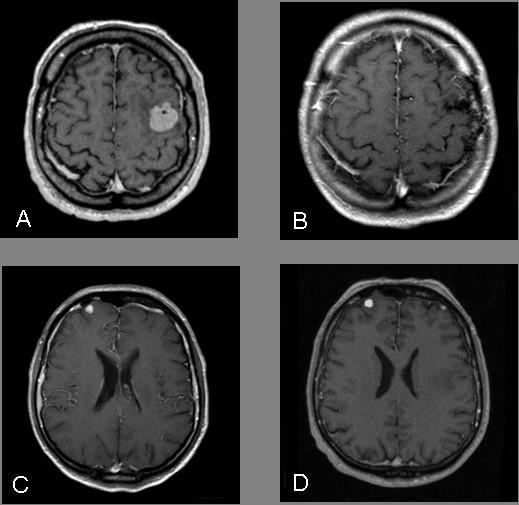

Magnetic resonance imaging demonstrated two intracerebral lesions. The symptomatic lesion was removed microneurosurgically and histology demonstrated a metastasis from a malignant peripheral nerve sheath tumor. Postoperatively, whole-brain irradiation was performed. The primary tumor was identified in the area of the sciatic nerve on the right. Follow-up 14 months after resection showed that there was no progression of the intracerebral lesions but an increase in size and number of distant metastases.

磁共振成像显示两个脑内病变。有症状的病变通过显微神经外科手术切除,组织学检查显示为恶性外周神经鞘瘤转移。术后进行了全脑照射。原发肿瘤在右侧坐骨神经区域被发现。切除术后14个月的随访显示,脑内病变无进展,但远处转移灶的大小和数量增加。